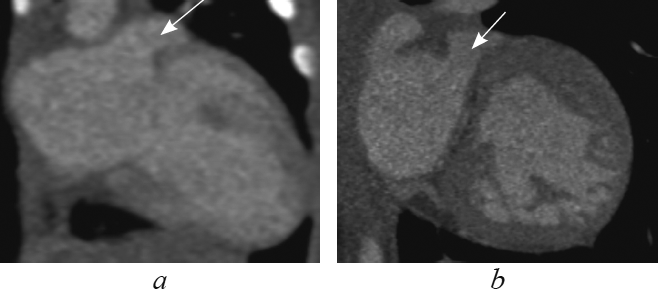

This article contents the results of computed tomography with intravenous bolus contrast media administration data analysis in children with transposition and congenitally corrected transposition of the great arteries with the consequental performing of the multiplanar heart-axis-oriented reformations. Among 148 examined children transposition of great arteries was detected in 13 patients (9 boys and 4 girls aged 1-144 day of life); congenitally corrected transposition was found in 4 cases of children aged from 6 months to 15 years and 6 months (2 boys and 2 girls). In this article comprehensive anatomical criteria of each heart chamber morphology are presented and reformations where these criteria can be seen are shown. Also in the article is given comparative characterization of heart and great arteries structures in transposition and congenitally corrected transposition in every certain heart-axis-oriented reformation. By the results of consequently performed heart-axis-oriented reformations data analysis the peculiar anatomical signs of transposition and congenitally corrected transposition are determined. The results of data analysis show that from the list of offered reformations the peculiar anatomical signs of both kinds of transposition are significantly determined in long-axis of right ventricle inflow tract reformation, left heart chambers reformation, supply ventricle division reformation, short-axis reformation at the level of great arteries. Computed tomographic angiocardiography heart-axis-oriented multiplanar reformations permit full and correct assessment of heart and main vessels, which is important for planning of surgical treatment in congenital heart diseases.